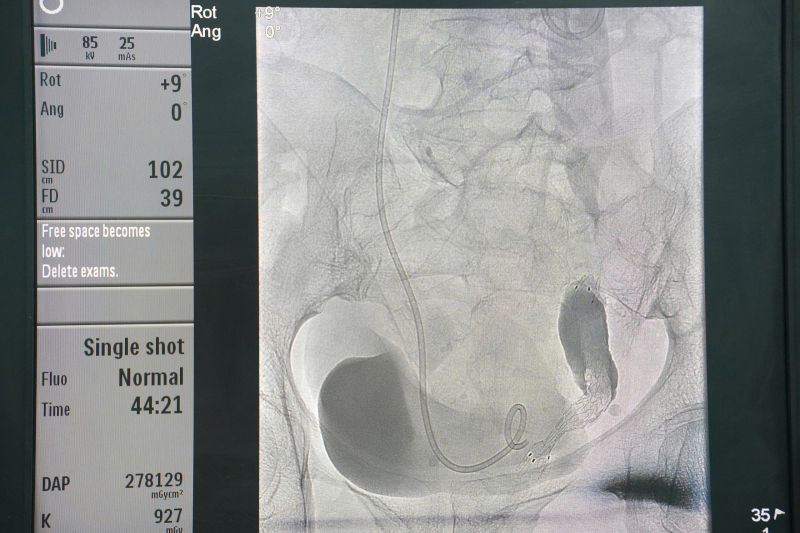

Hình ảnh: stent niệu quản trên hệ thống chụp mạch số hóa xóa nền (DSA).